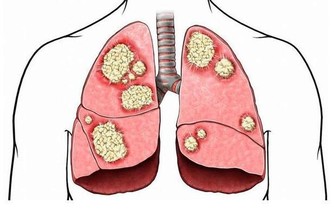

肝膽開始回血,把有毒的血過濾掉,產生新鮮的血液,到一百歲也沒有膽結石,也沒有肝炎、囊腫一類的病。

如果你天天熬夜到 1 點多,肝回不了血,有毒的血排不掉,新鮮的血生不成,膽又無法換膽汁,

所以這些人容易得膽結石、囊腫、大三陽、小三陽各種病癥。